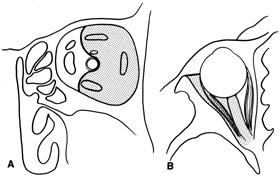

Valuable information about the nature and extent of an orbital pathologic process is provided by imaging studies such as computed tomography (CT) scan, magnetic resonance imaging (MRI), and orbital echography. Better spatial resolution, ready accessibility, and lower cost make CT the preferred choice for orbital imaging in most cases. Orbital fat provides a natural contrast between most adjacent orbital structures on CT scanning, and orbital bones are visualized well. Computed tomography is essential for evaluation of the orbital bones because they cannot be imaged with MRI. Direct coronal or sagittal images are important to identify the relationship of a lesion to the optic nerve so that the surgical approach can be planned to avoid traversing the optic nerve (Fig. 1).

Fig. 1. A. Axial CT scan demonstrating a large, well-encapsulated lesion in the orbital apex. Coronal (B) and sagittal (C) scans demonstrate that the mass lies inferior and medial to the optic nerve within the intraconal space. This information is useful in planning the surgical approach to the mass, which should avoid traversing the optic nerve.